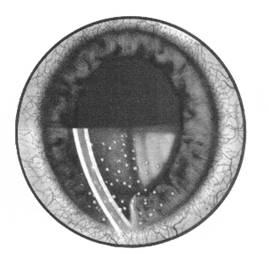

precipitate pe fata posterioara a corneei (pe endoteliu). Aceste precipitate sunt depozite alcatuite din celule inflamatorii care se depun pe endoteliu datorita curentului din umoarea apoasa. Ele constituie elementul obligatoriu pentru diagnosticul de ciclita (Fig. 12.1).

Fig. 12.1 - Precipitate retrocorneene